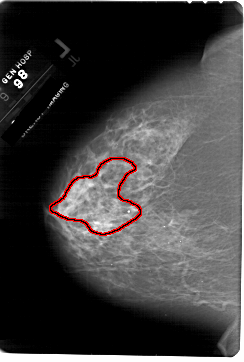

FILE: A_1817_1.LEFT_CC.OVERLAY

TOTAL_ABNORMALITIES 1

ABNORMALITY 1

LESION_TYPE CALCIFICATION TYPE PLEOMORPHIC DISTRIBUTION SEGMENTAL

ASSESSMENT 4

SUBTLETY 4

PATHOLOGY MALIGNANT

TOTAL_OUTLINES 1

BOUNDARY